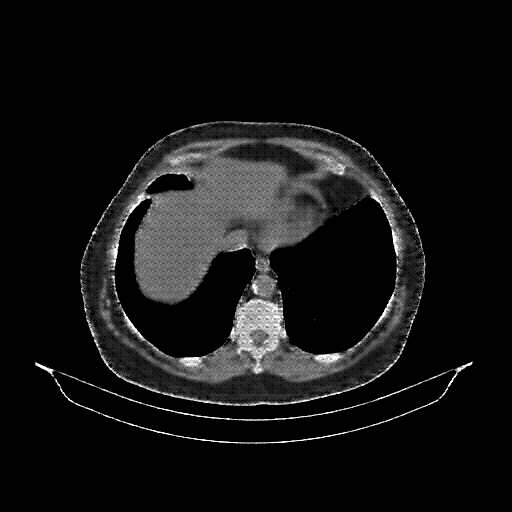

Original NATIVE CT scan (input)

Full window (WL 1023.5, WW 4095 β†’ Low βˆ’1024, High +3071)

Reconstructed NATIVE CT scan (cycle consistency)